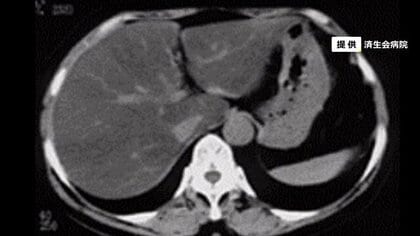

「肝臓」脂肪が急増…コロナ禍の運動不足も原因?放置すればがんの恐れも 予防法をご紹介【福井発】

福井テレビ

ライフ

2022年5月15日